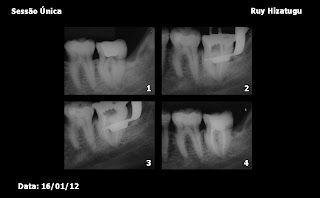

WORKSHOP CIOSP

2012

Endodontia em molares em

Sessão Única

Coordenador: Ruy

Hizatugu.

Protocolo:

1. Anestesia;

2. Acesso; 3. Modelagem e Limpeza (clorexidina gel 2% + irrigação ultrassônica

- soro fisiológico + EDTA 17%);

4. Obturação - Condensação

vertical - Schilder - AH-Plus; 5. Blindagem - Resina

composta

P.S.: Pós-operatório: 12 horas - Dor leve

controlada com analgésico (1 comprimido Tylenol) / 24 horas - Sem dor / 72 horas

- Sem dor;

Prognóstico:

Favorável